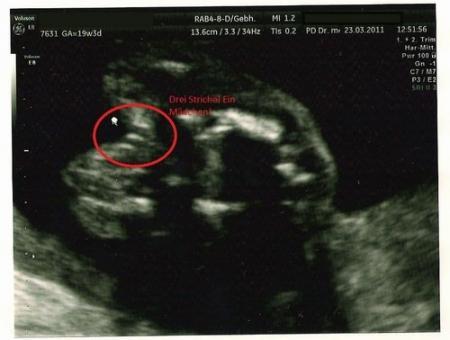

Ich habe auch so eins. Also man kann die striche schon vertrauen

Also könnte man sagen, 2 Striche ein Junge 3 Striche ein Mädchen ?? oder wie jetzt ??

Ja :) so hat's mein Hausarzt gesagt.

Schön :) es ist ein Mädchen! Hab auch eins gesehen im Internet so wie es bei mir ausgesehen hat :) und es ist ein Mädchen..

Die 2 Striche auf dem Bild sind ja quer, und sehen für mich nach Hoden aus. Bei Mädchen sind es Längs-Striche (ob 2 oder 3 kann man wahrscheinlich nicht immer so genau sehn).